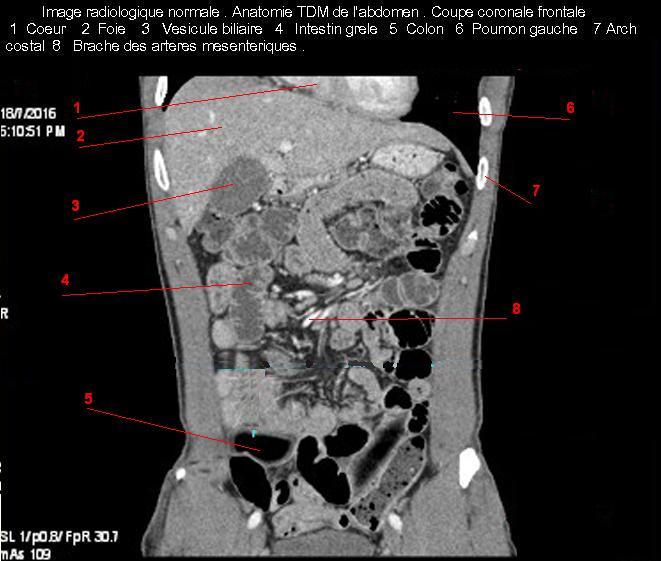

Images radiologique TDM normale de l'abdomen et tube digestif en coupe frontale ( Coronale )  :